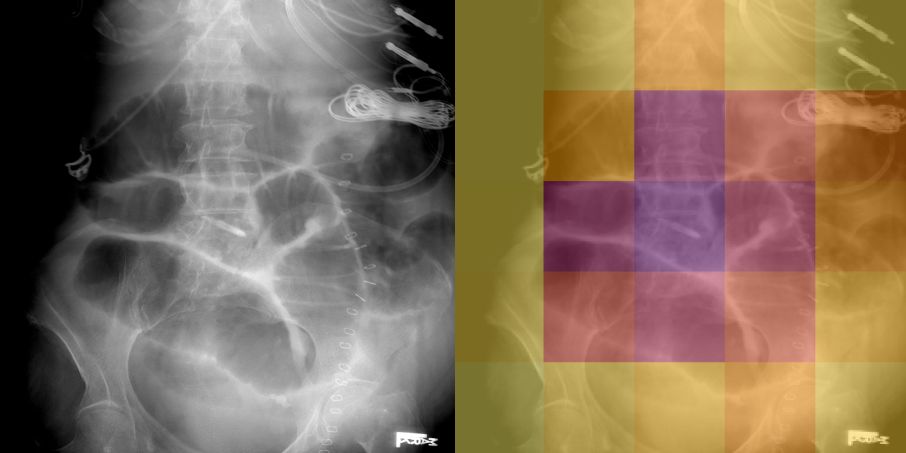

Detection of High-Grade Small Bowel Obstruction on Conventional Radiography with Convolutional Neural Networks

Studies of deep learning applied to abdominal radiographs. We show that transfer learning can be used to create a classifier for detection of high-grade small bowel obstruction patterns on supine abdominal radiographs.

Phillip Cheng, Tapas Tejura, Khoa Tran, Gilbert Whang

Abdominal Radiology 2018 (pilot study)

Am J Roentgenology 2019 (increased training)